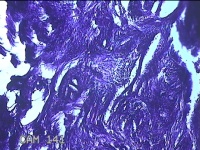

宫腔赘生物

性别

女

年龄

40岁

临床诊断

子宫内膜息肉?

一般病史

不规则阴道流血12天。

标本名称

大体所见

灰白暗红色不规则碎组织1.5x1.2x0.7cm一堆。